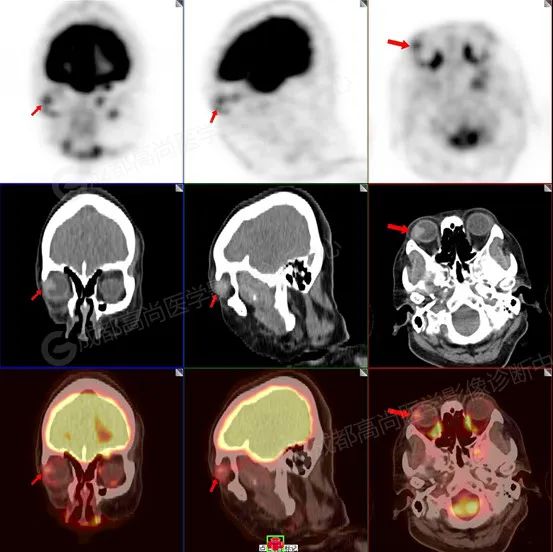

图 1-3 检查所见:紧贴右侧眼球外侧壁类三角形高密度结节突入玻璃体内(大小约 1.0 cm×1.1 cm×1.2 cm),邻近外侧和后侧眼环轻度增厚,FDG 代谢轻度增高,提示多为恶性肿瘤性病变,请结合病理。

脉络膜黑色素瘤病灶多见于眼球后壁及颞侧壁, 以隆起性形态 (半球形、蕈状、结节状) 为主。有较高的隆起高度,具有特征性 T1WI 高、T2WI 低信号,增强有强化。18-F FDG 显像均匀不同程度代谢增高,全身其余部位未见确切原发病变。